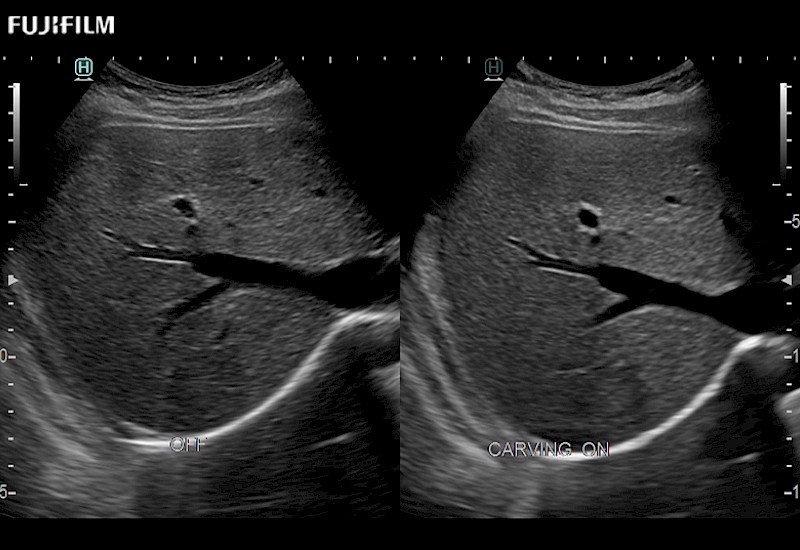

Extraordinary high-resolution digital imaging

Multi-Parametric imaging modalities